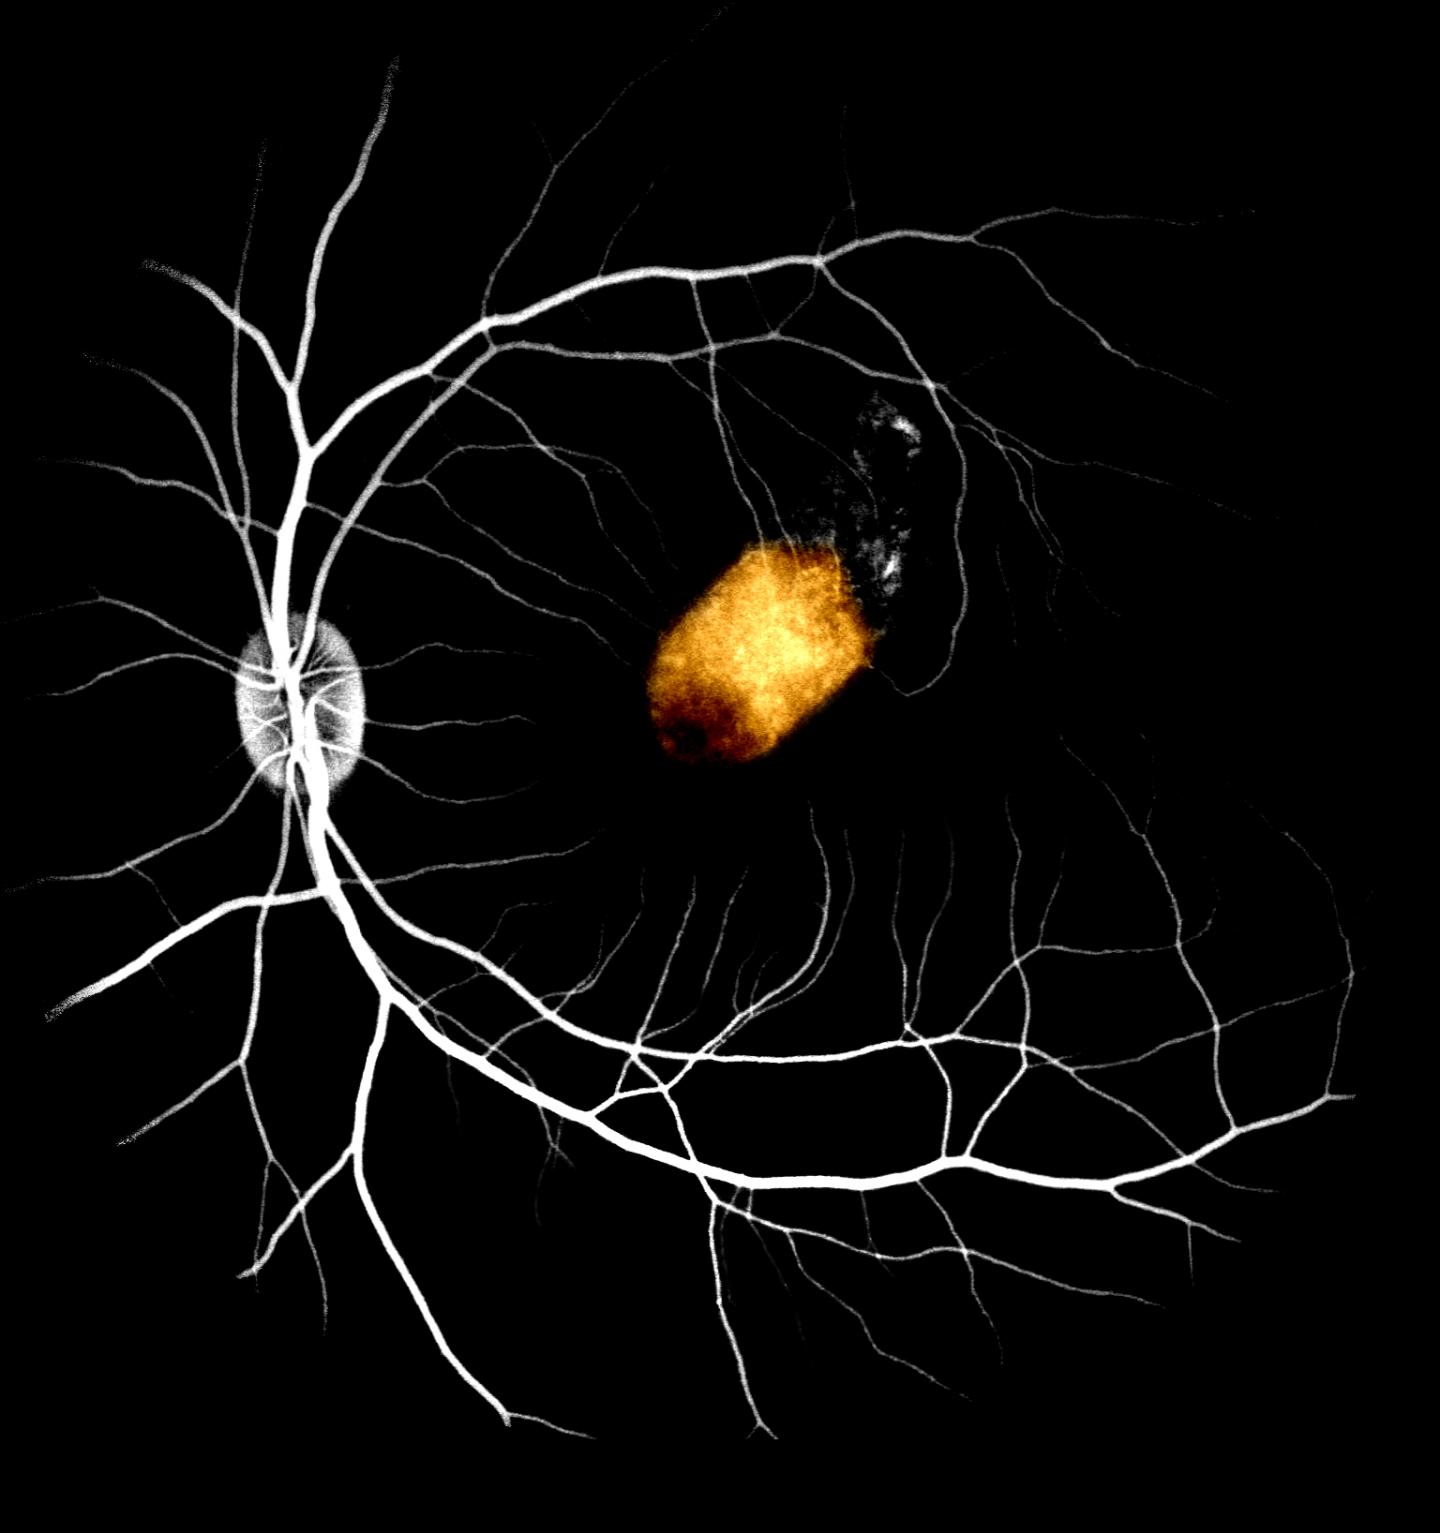

Retinal cells derived from adult human eye stem cells survived when transplanted into the eyes of monkeys, an important early step in the validation of this approach for treating blindness, according to a study by Liu, et al recently published in Stem Cell Reports . The retinal pigment epithelium (RPE), a layer of pigmented cells in the retina, is essential for sustaining normal vision. Blindness due to RPE dysfunction, such as macular degeneration, affects about 200 million people worldwide.

To restore this population of cells, researchers extracted retinal stem cells from donated cadaver adult eyes, grew them into RPE cells and transplanted them into the eyes of monkeys. These unique cells have the potential to serve as an unlimited resource of human RPE, with the possibility of donor compatibility matching.

The study is the first time the safety and feasibility of adult retinal stem cell-derived RPE transplants in non-human primates was assessed. Researchers found that RPE patches transplanted into the monkey's eye stably integrated for at least three months with no serious side effects. What is more, the stem cell-derived RPE partially took over the function of the monkey RPE and was able to support normal photoreceptor function. Importantly, these cells did not cause retinal scarring.

Altogether, this demonstrates the feasibility of using adult retinal stem cell-derived RPE transplants to replace defective RPE as a possible treatment for macular degeneration. However, further experiments need to be conducted. This includes evidence to demonstrate adult retinal stem cell-derived RPE can restore vision in diseased non-human primate models, and eventually in regulatory human clinical trials. Nonetheless, this proof-of-principle study is an important early step in validating this approach, which is part of as international collaboration between the Icahn School of Medicine at Mount Sinai (New York), Institute of Molecular Cell Biology (A*STAR), Singapore Eye Research, National University of Singapore, and Eye Clinic Sulzbach (Germany).